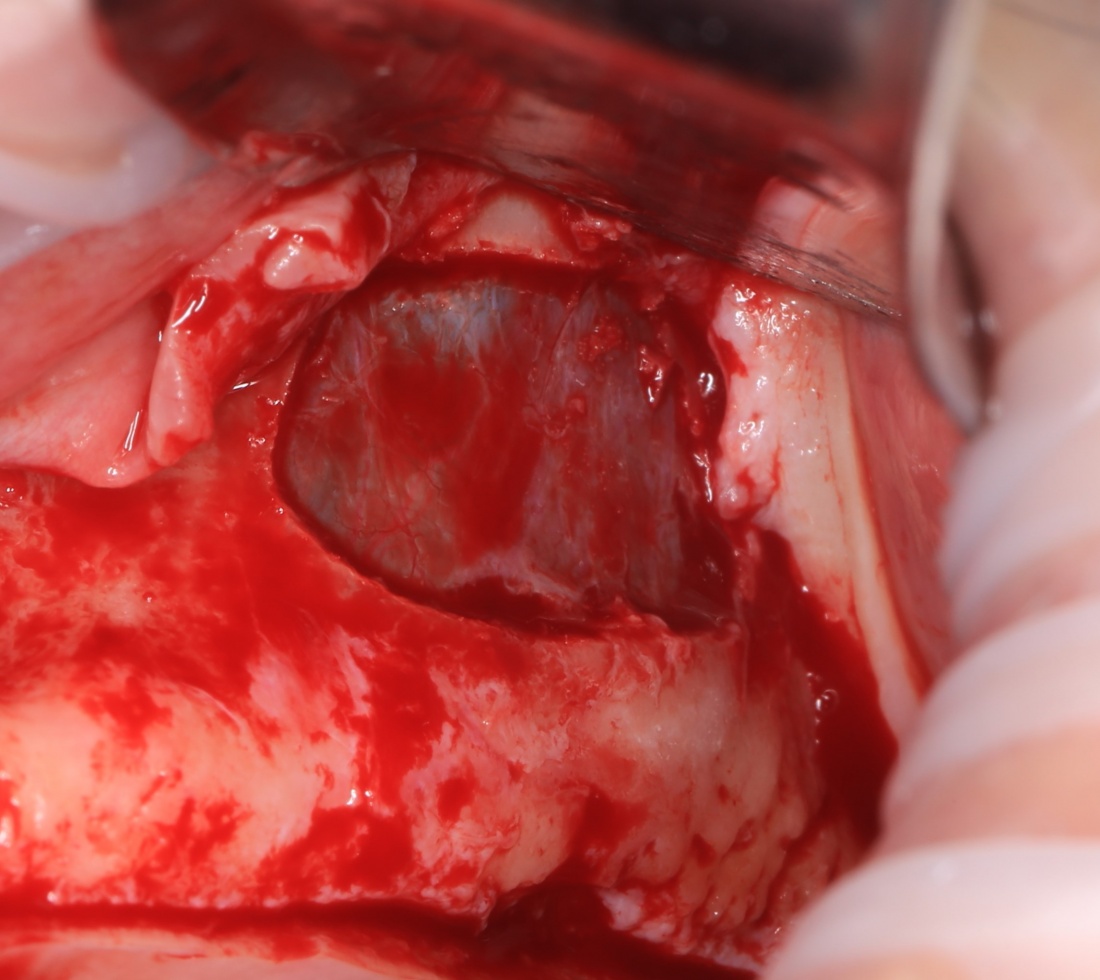

Для получения костного блока, мы открываем донорскую зону, наружную косую линию нижней челюсти.

Получение костного аутотрансплантата.

Здесь потребуется пародонтологический зонд с миллиметровой разметкой или какой-то другой измерительный прибор (операционная линейка). Ранее по КЛКТ я измерил костный дефект, теперь нужно нанести границы будущего костного блока на донорскую зону.

Ремарка: некоторые доктора предлагают делать хирургические шаблоны или выкройки специально для точного забора костного блока. На мой взгляд, это чрезмерное усложнение - во-первых, использование подобных шаблонов или выкроек требует увеличения площади раны, во-вторых, это увеличивает время и стоимость лечения, в-третьих, на этом этапе не требуется высокая точность, поскольку блок всё равно потребует адаптации.

Иными словами, важна не точность, а быстрый, аккуратный и, что главное, малотравматичный забор аутотрансплантата.

Для получения костного блока мы использовали ультразвуковую пьезохирургическую систему. Это самый удобный и безопасный инструмент для проведения подобных манипуляций. С помощью него мы сформировали и выделили костный блок. Он должен отделяться легким движением остеотома или элеватора. Как это сделать правильно — читай здесь>>